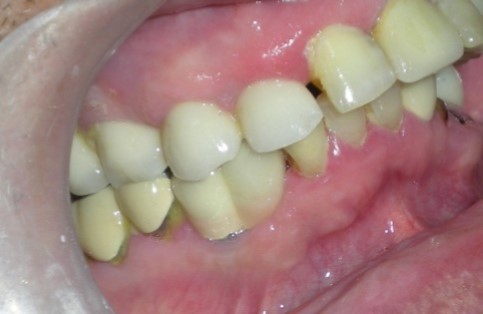

The separator spray (Detax, Germany) was applied around the impression copings (Figure 7) before the application of artificial gingiva (Esthetic mask, Detax, Germany) for easy separation of artificial gingiva from impression material as both are silicones. The artificial gingiva was applied around impression copings and the impression was poured with type IV gypsum product ((Kalstone; Kalabhai Karson Pvt. Ltd. India) to obtain the master cast (Figure 8), which, with a soft tissue gingival mask, will allow the restorative dentist and technician to choose the ideal abutment and technique for the case. Further , the accuracy of the impression was verified with verification jig. the verification jig should fit passively on the cast as well as in patient mouth. After verification jig trial, the prosthesis (two joined PFM crowns, Figure 9 and Figure 10) was fabricated over two modified castable UCLA abutments (PLA-R straight plastic abutments, AlphaBio, Israel). The final prosthesis was cemented with chemical cure resin cement.

Figure 9.Radiograph verifying the fit of the abutment